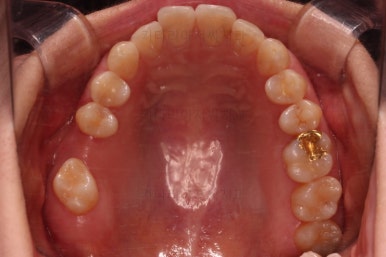

이번 환자분이 선택한 앞니 부분교정 장치는 MTA라는 장치인데요.

부분교정에 좀 더 특화된 부피가 작고 심미적인 장치입니다.

물론 철사는 들어가고요.

어금니쪽은 쓰러진 어금니를 원위치 시키기 위해서 미니스크류를 식립하여 준비작업을 해줍니다.

어금니 위치 조절을 계속 해주고요.

아래 앞니는 부분교정에 필수인 치간삭제를 병행하면서 많이 가지런해지고 있습니다.

아랫니 부분교정이 끝났고요.

어금니도 원위치로 많이 갔네요.